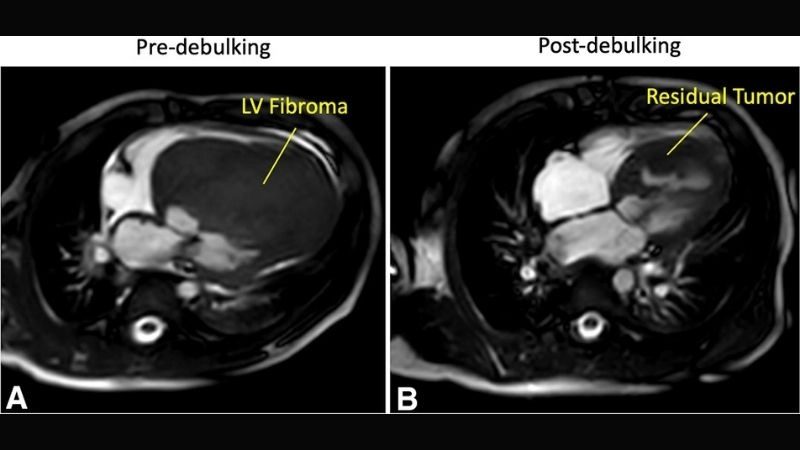

Images visual examples of cardiac fibroma

Cardiac fibroma is a rare, benign tumor of the heart composed mainly of fibrous tissue. It often develops in children and may cause symptoms related to heart rhythm and pumping function.